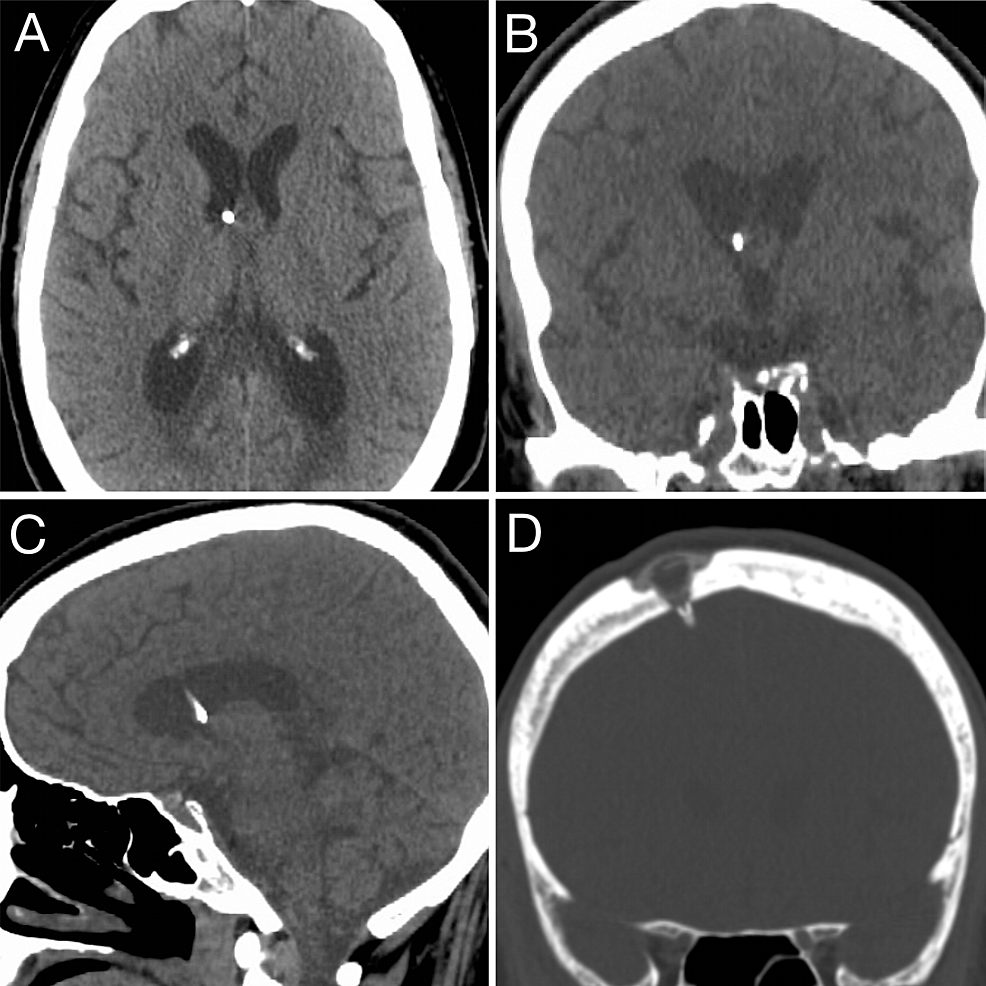

(PDF) Ommaya Reservoir Integrity Computed Tomography Evaluation · Computed Tomography Reservoir Ommaya Definition It is about the size of a. It allows the care team to take samples of their spinal fluid and. an ommaya reservoir is an intraventricular catheter system that can be used for the aspiration of cerebrospinal fluid or for the. It’s about the size of a quarter. an ommaya reservoir (intraventricular reservoir) is a device placed next. Reservoir Ommaya Definition.